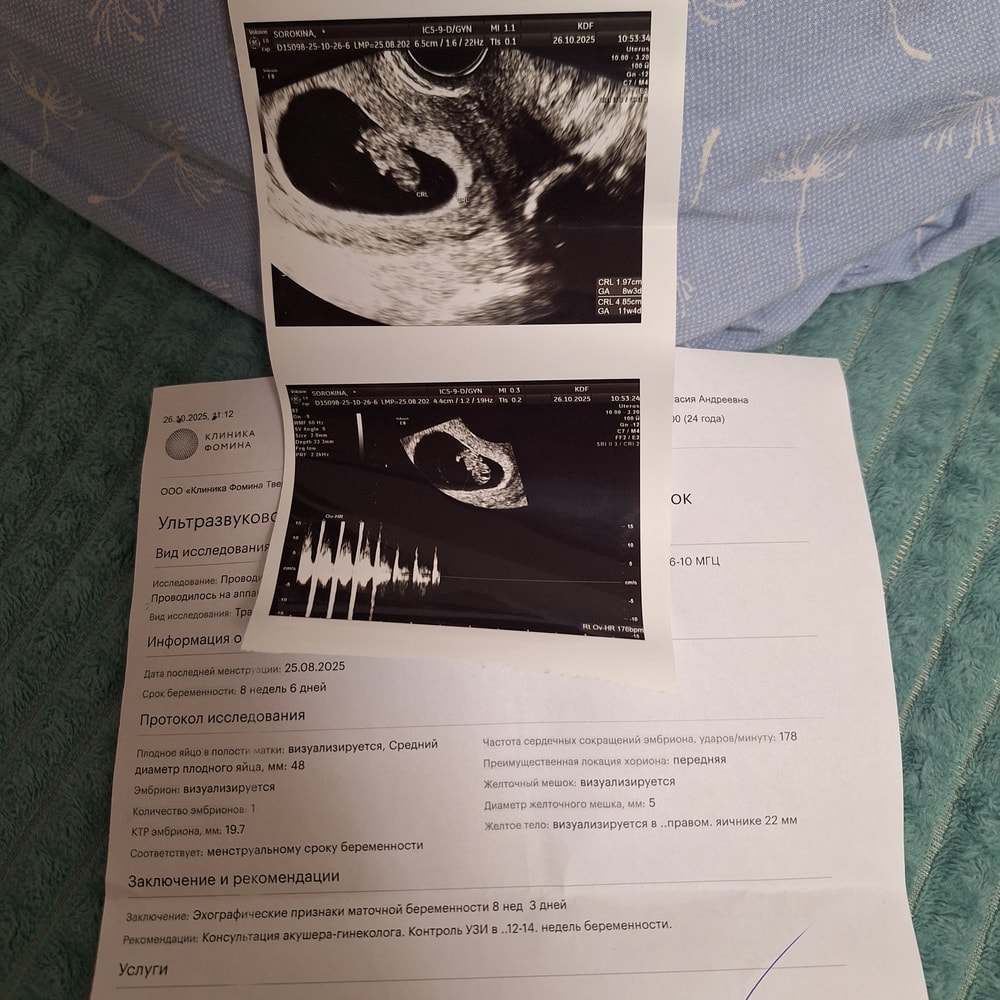

Девочки привет! У меня 8+6 недель, токсикоз начался где-то с 6 недели, в 8 недель резко пропал токс и до сих пор, никаких беременных симптомов, кушаю все, не устаю. Начала переживать, неделю думала, что накручиваю себя, в последний день не выдержала, сходила на УЗИ. Меня успокоили, сказали все хорошо с малышом, послушала сердечко. 🙏

Была сегодня на УЗИ, подтвердили маточную беременность.

5 недель и 2 дня

ПЯ 6,0 мм

ЖМ 1,9 мм